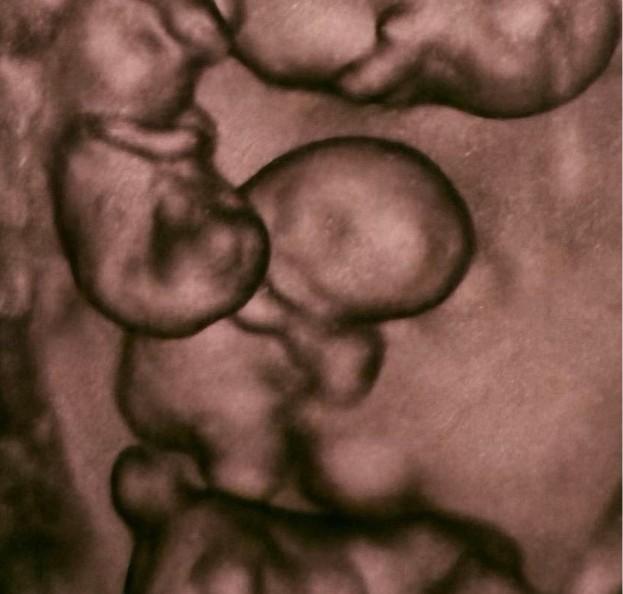

Однояйцевая беременность — это развитие двух или более эмбрионов из одной оплодотворенной яйцеклетки (зиготы), которая разделилась на ранней стадии. Такие дети генетически идентичны: они всегда одного пола и внешне очень похожи. В большинстве случаев у них общая плацента.

Монохориальная беременность — подвид однояйцевой беременности. Ее главная особенность в том, что все эмбрионы делят одну общую плаценту (хорион). Из-за общей сосудистой системы плаценты такие беременности считаются высокорисковыми и требуют частого УЗИ-мониторинга (каждые 1-2 недели).